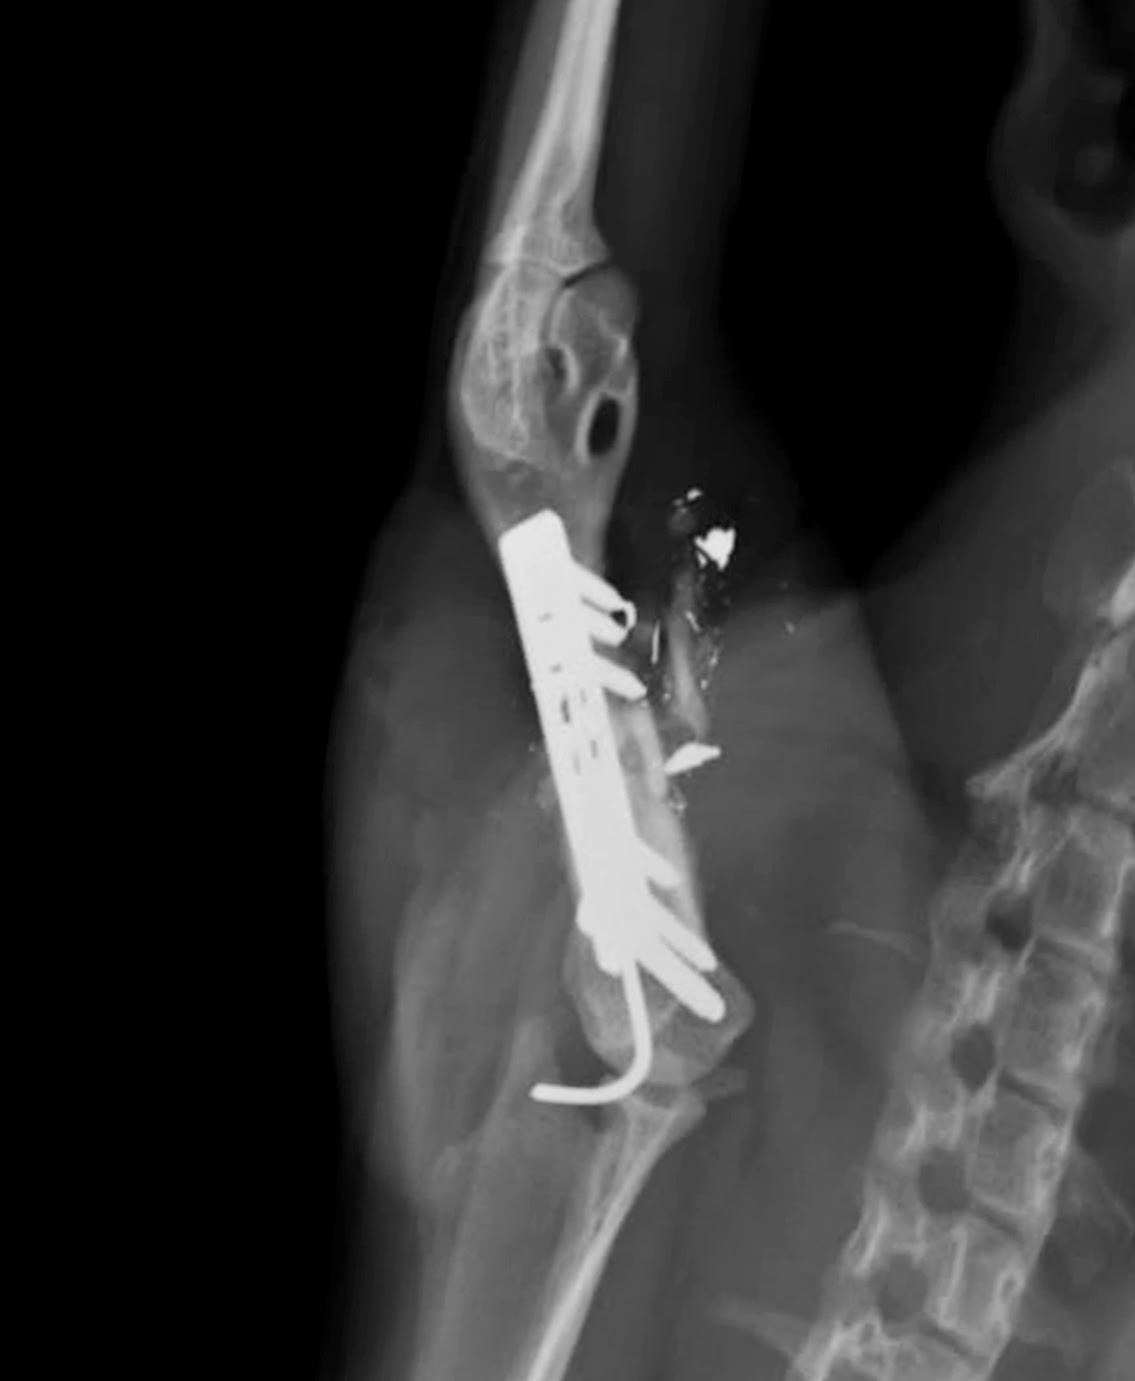

Comenzamos

el estudio radiológico con una vista ventro dorsal del brazo y obtenemos esta

primera imagen:

Aunque es

un poco desconcertante podemos concluir que hay una fractura de húmero, que los

extremos están desplazados y que el paciente ha recibido un disparo de un

perdigón de plomo que se ha roto dentro, y todavía conserva los fragmentos.

Necesitamos la otra vista radiográfica para saber más, y se realiza la

siguiente radiografía: